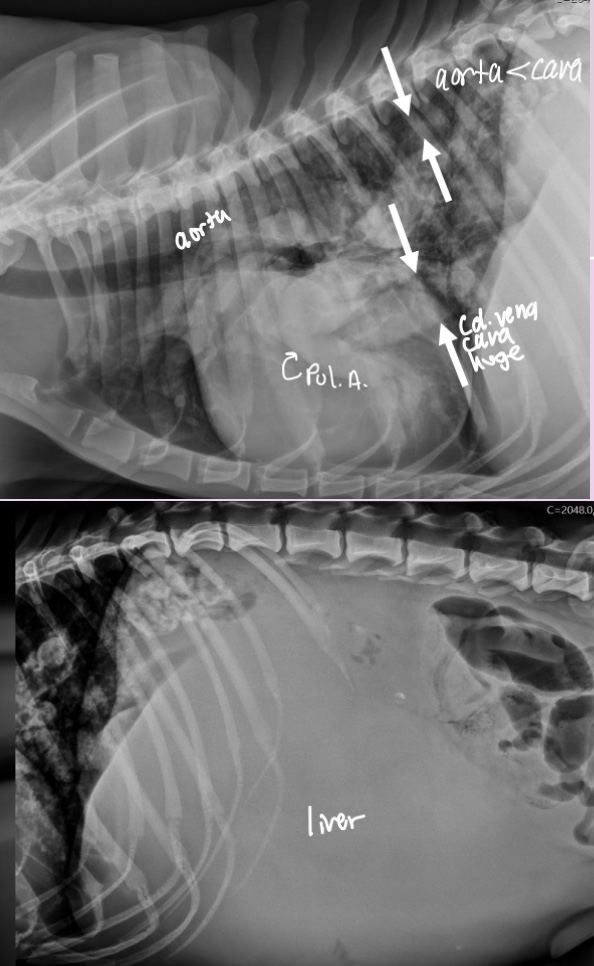

Enlargement of MPA is associated with what 2 pathologies

-pulmonary hypertension

-dz of pulmonary outflow tract (pulmonic stenosis, heartworm)

**mild MPA enlargement can be normal in some dogs - eval in light of other findings**

Roentgen signs of pulmonic stenosis

-Right heart enlargement (RVE +/- RAE) d/t PRESSURE OVERLOAD

-MPA enlargement

-Normal to small pulmonary vessels (hypoperfusion)

+/- RHF

pathogenesis of pulmonic stenosis

1.Narrow pulmonic valve

2.RV hypertrophies to try and muscle the blood through narrow valve

3.dilation of MPA after the stenotic region

What does the angiocardiography highlight in pulmonic stenosis

-RV hypertrophy

-narrowing pulmonary outflow tract

-post-stenotic dilation of MPA segment

What disease does this dog have

Pulmonic stenosis